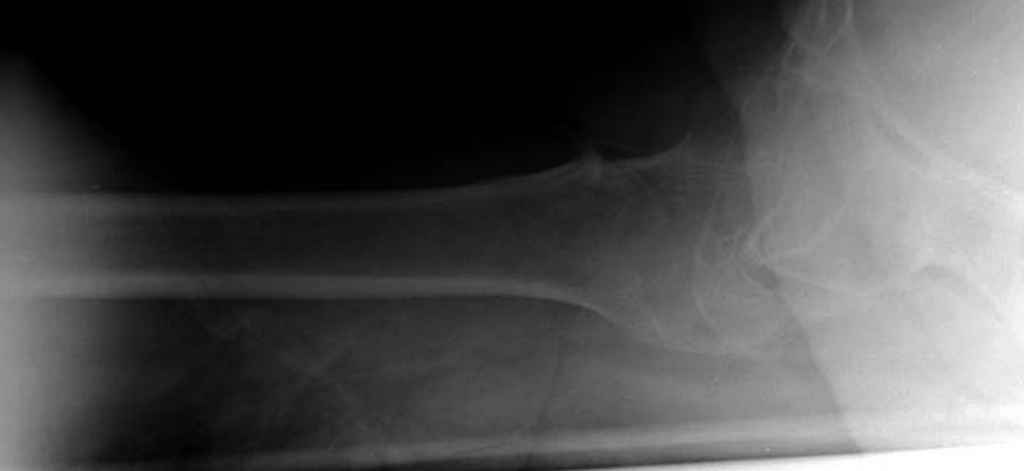

В данном случае в головке бедра и в вертлужной впадине огромный дефект, навряд ли удалением импланта или заменой на другой можно сохранить сустав.

Вашему вниманию представляется похожий случай, пациентке 70, осложнился в течение одного месяца после операции. Ревизия с заменой сустава, кабельная фиксация на трохантер. При установке в дистальном диафизе обнаружен тонкий кортикальный слой и сделана профилактика от возможного перелома аллографтом.